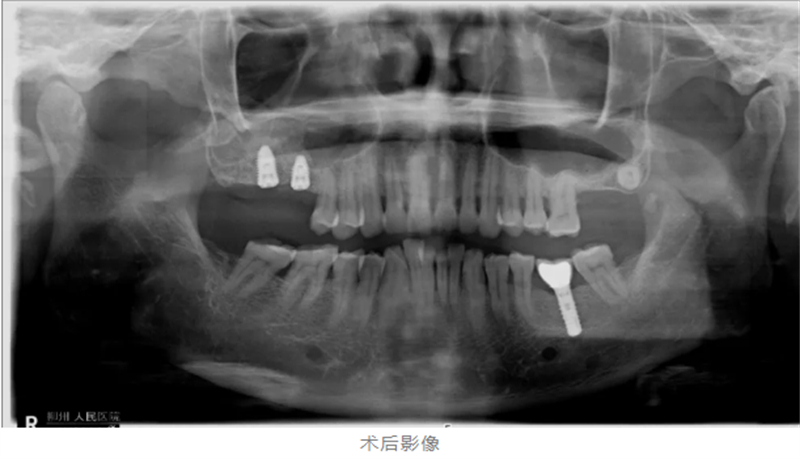

口腔科種植團隊為黃阿姨進行了全面檢查,影像學結果顯示,其雙側上頜后牙區(qū)牙槽骨吸收嚴重——左側牙槽骨厚度僅1.6mm,右側也僅約3mm,遠不能滿足常規(guī)種植牙植入所需骨量。

在局麻狀態(tài)下,手術團隊通過側壁開窗,提升竇底黏膜,植入骨粉,成功將骨厚度增至7-8mm,為種植體穩(wěn)定性奠定了堅實基礎。